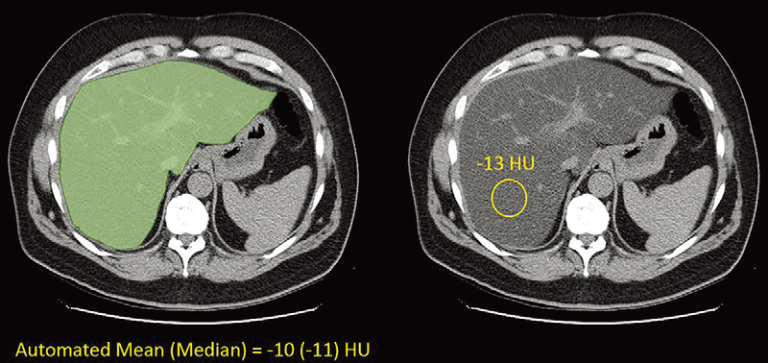

业务学习|人工智能|病理|脂肪肝 在平扫腹部 CT 中自动进行肝脂肪定量—基于人群的脂肪变性评估 作者Dr_F_LIU 2022-10-142022-10-14 背景 非酒精性脂肪性肝病及其后果是一个日益严重的公共卫生问题,需要横断面成像以进行无创诊断和肝脏脂肪定量。 目…